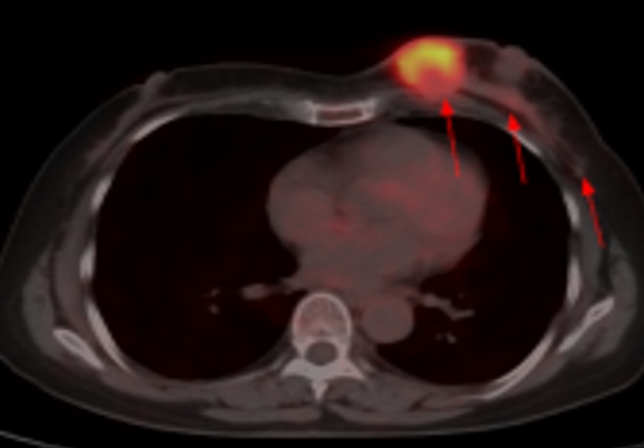

吉林省肿瘤医院

吉林省肿瘤医院始建于1984年,是全省唯一集医疗、教学、科研、预防为一体的大型现代化三级甲等专科医院,是“吉林省癌症中心”挂靠单位和“国家临床肿瘤重点专科建设项目单位”。医院承担国家肿瘤防治重任,是吉林省规模最大、技术力量最雄厚的肿瘤防治中心。医院现有湖光院区、高新院区两个院区,编制床位1498张……【详情】